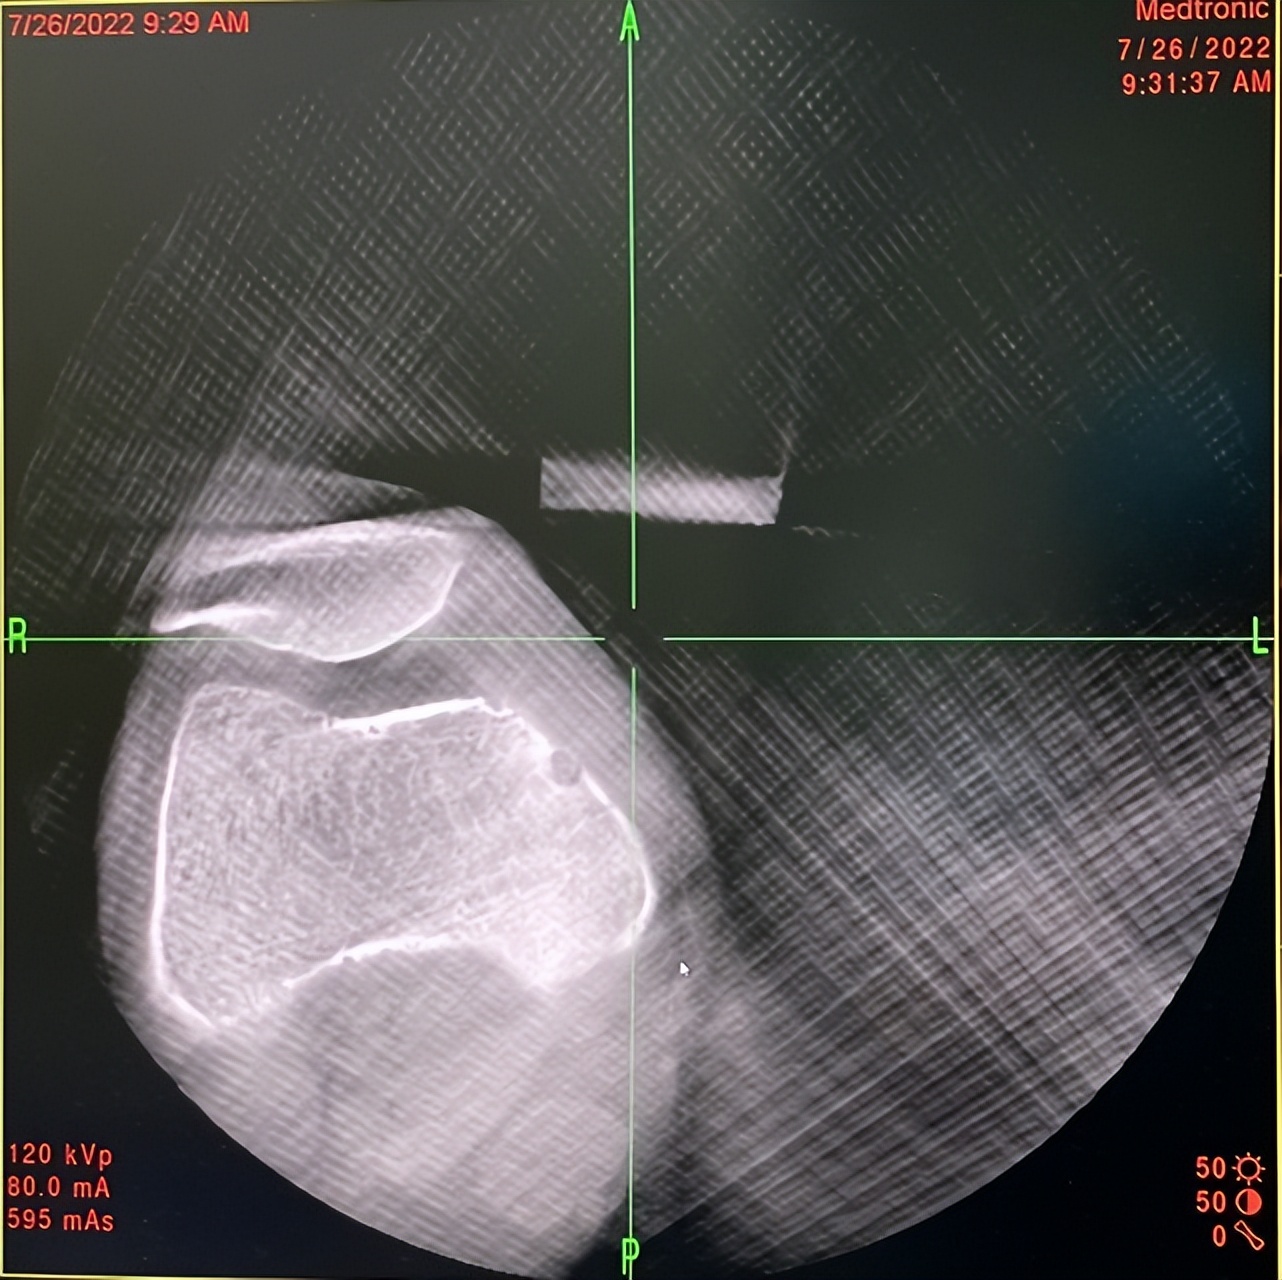

术中O型扫描肿瘤影像

微波针置入瘤巢进行热消融

杨团民主任带领团队进行手术,将一根直径为2mm的微波消融针在计算机导航及机器人辅助下精确置入骨样骨瘤瘤巢核心,对肿瘤实施高温热消融治疗。半个小时后,手术顺利完成。